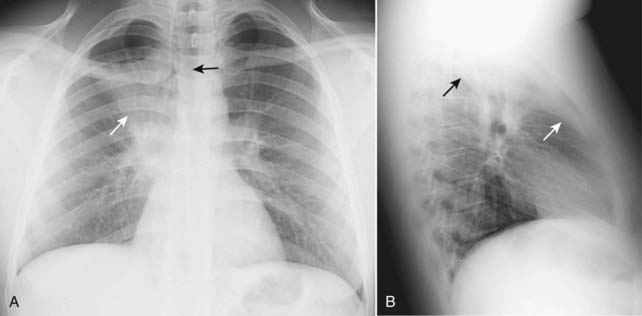

Figure 5-1 Right middle lobe atelectasis.

Frontal (A) and lateral (B) views of the chest show an area of increased density (solid white arrow), which is silhouetting the normal right heart border (solid black arrow) indicating its anterior location in the right middle lobe. On the lateral view (B), the minor fissure is displaced downward (dotted white arrow) and the major fissure is displaced slightly upward (dotted black arrow). Note the anterior location of the middle lobe.

image Right middle lobe atelectasis (see Fig. 5-1)

On the frontal radiograph:

There is a triangular density with its base silhouetting the right heart border and its apex pointing toward the lateral chest wall.

The minor fissure is displaced downward.

On the lateral radiograph:

There is a triangular density with its base directed anteriorly and its apex at the hilum.

The minor fissure may be displaced inferiorly and the major fissure superiorly.